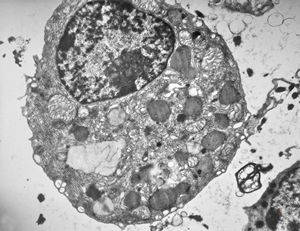

bone marrow - crystalloid inclusions Charcot-Leyden crystals formation

bone marrow - crystalloid inclusions Charcot-Leyden crystals formation v.s.